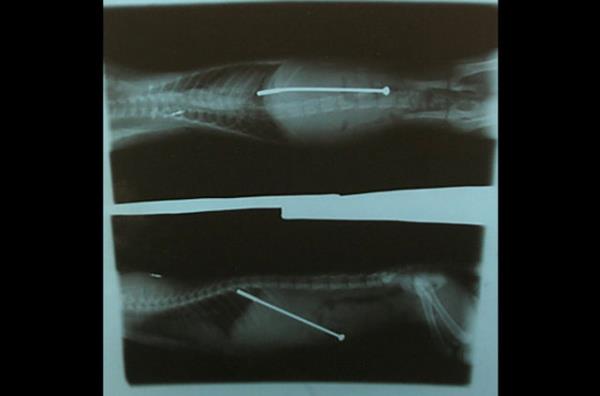

9. 10 yaşındaki Husky cinsi bu köpek oynarken yuttuğu çatal yüzünden büyük bir tehlike atlattı. Midesi delinen köpek ameliyat edilerek kurtarıldı.

10 yaşındaki Husky cinsi bu köpek oynarken yuttuğu çatal yüzünden büyük bir tehlike atlattı. Midesi delinen köpek ameliyat edilerek kurtarıldı.